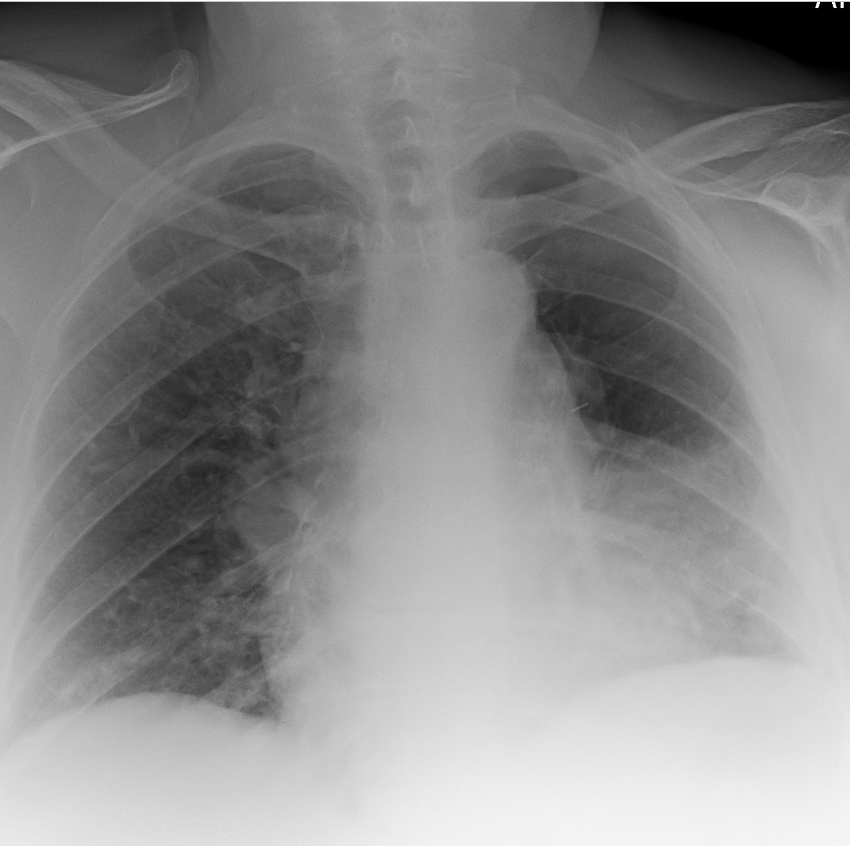

What is this ?

Cardiac failure